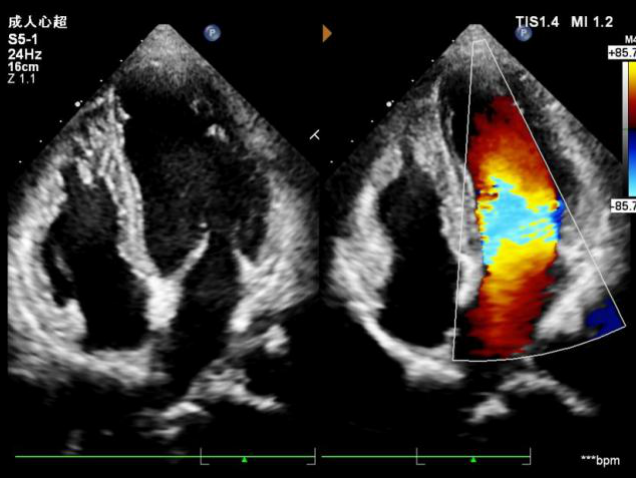

还有一些孕妇,本身就有先天性心脏病,有的已经做过手术,有的还没有做手术,在孕期母体的心脏负担比较大,需要监测心脏结构、功能有没有变化,就需要做心脏超声了。另外还有孕妇本身就有甲状腺疾病等,除了化验甲功以外也需要结合超声检查来评估甲状腺情况,因为母体甲状腺是否正常对于胎儿发育也是非常关键的。

正常心脏四腔心及二尖瓣口血流信号